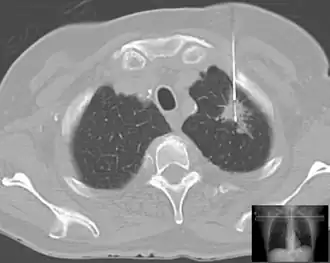

| Lung | Biopsies of the lung can be performed in a variety of ways depending on the location. |